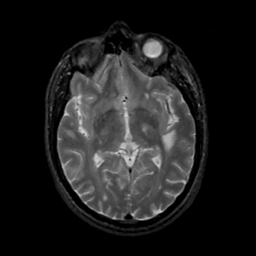

MR Study #12, May 12, 1991 -- Slice #24